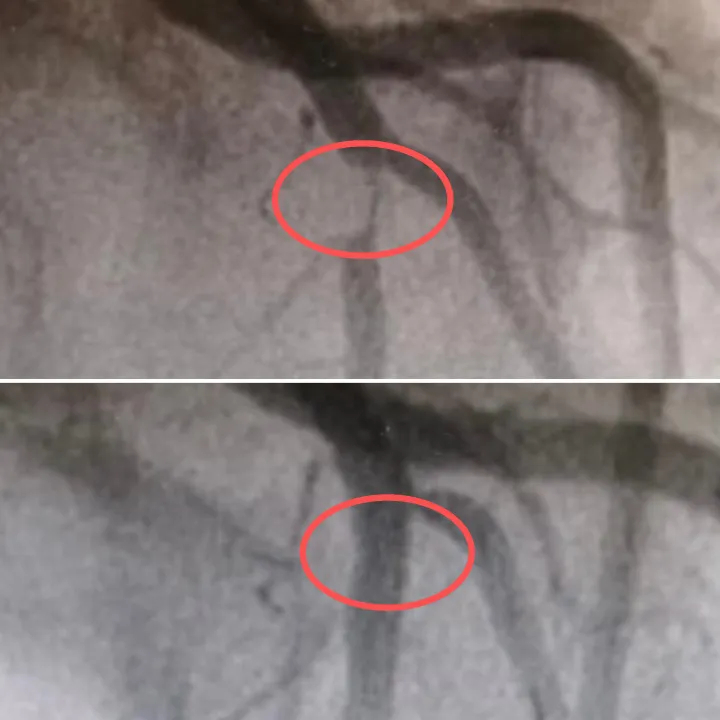

Kết quả chụp mạch máu sau đó khiến các bác sĩ bất ngờ, mạch máu quan trọng nhất trong tim, nhánh động mạch vành trái trước... bị tắc nghẽn đến 95%, chỉ còn một khe hẹp cung cấp máu, và luôn có nguy cơ bị tắc nghẽn hoàn toàn. Mạch máu này giống như "động mạch chính" của tim; nếu bị tắc nghẽn, nó sẽ gây ra nhồi máu cơ tim nghiêm trọng .Hậu quả sẽ không thể tưởng tượng nổi.

Các bác sĩ đã tiến hành cấy ghép thành công một stent vào mạch máu bị tắc của Tiểu Vân, mở rộng đoạn mạch hẹp, khôi phục nguồn cung cấp máu cho tim và cứu cô khỏi "bờ vực".